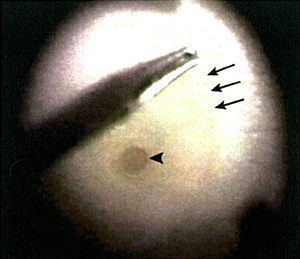

黄斑点穿孔是指黄斑点中央的凹位失去视觉神经组织,此情况大多由於老化或深近视所致。治疗方法是施行扁平部玻璃状体切除术,移除凹前表质玻璃体,并进行气体和液体交换。大部份病人在手术後无须保持俯卧。患上黄斑穿孔的年长及深近视人士现时可以最新手术移除内界膜(图1)治疗,手术成功率超过90%。

![]() 图1:手术期间的情况(从医生的角度望向患者左眼):利用眼内手术夹,在已形成的黄斑点穿孔(箭头所指位置)附近夹起内界膜(箭头所在位置)。 |